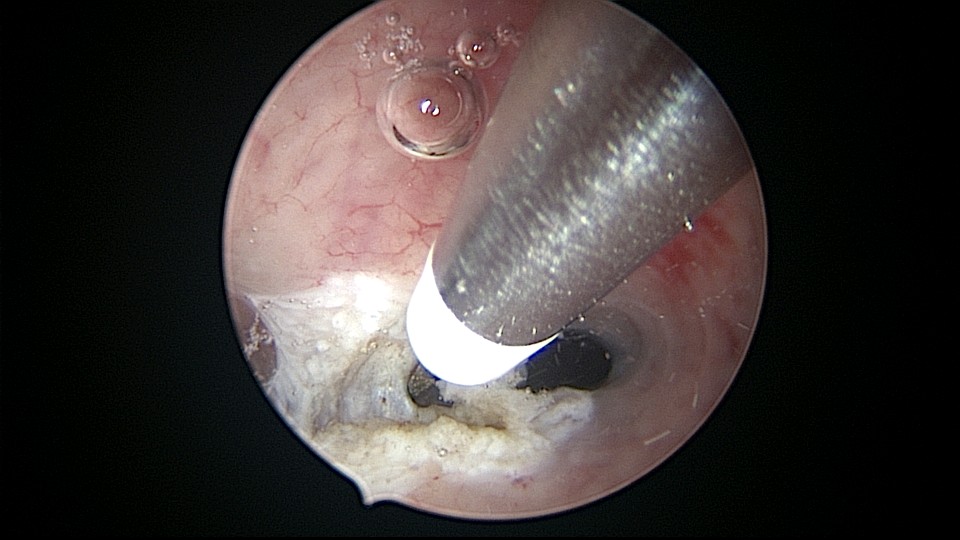

患者32岁,G2P0,自然流产2次,外院行清宫术,术后月经量减少一半。2019年6月市妇幼分粘,术后月经无改善,宫腔粘连复发,2020年11月宫腔镜探查,宫腔中上段幕状粘连,形成两个假的输卵管开口,双极电针分粘,恢复宫腔形态,显露正常的输卵管开口。2020年12月宫腔镜二探取球囊,宫腔形态正常,双侧输卵管开口可见,内膜充血。2022年5月自然妊娠,2023年1月剖宫产分娩一女婴(37+2)。现37岁,G3P1。